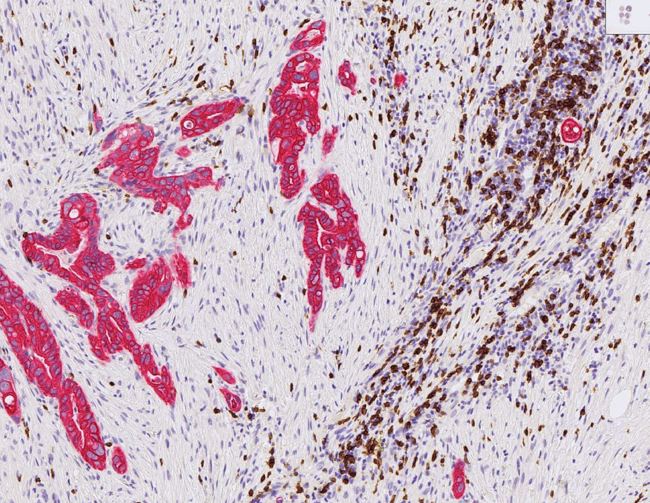

Helen och Laia studerar kroppens egna immunförsvar i form av T-celler. Dessa T-celler ska försvara kroppen mot cancer, men vid tumörer i bukspottskörteln hämmas deras aktivitet. Anledningen är att det bildas ett tjockt lager av bindvävceller (cancerassocierade fibroblaster) runt tumörerna som förhindrar att T-celler ens förflyttar sig mot tumörerna. Fibroblasterna förhindrar även kemoterapi.